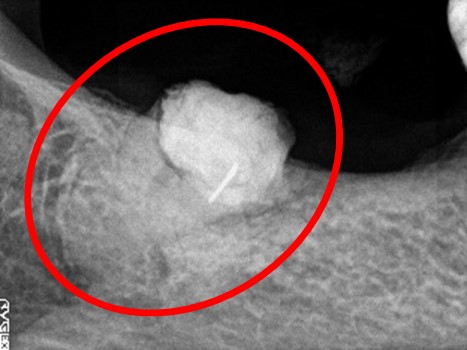

レントゲンで詳しく診てみると、歯根が真っ二つに割れていることがわかりました。臭いは、割れているために炎症を引き起こし、そこからの膿が原因でした。保存することができず抜歯しました。抜歯後、インプラントを埋入しました。

歯根が真っ二つに割れていました

抜いた歯

【抜歯後】